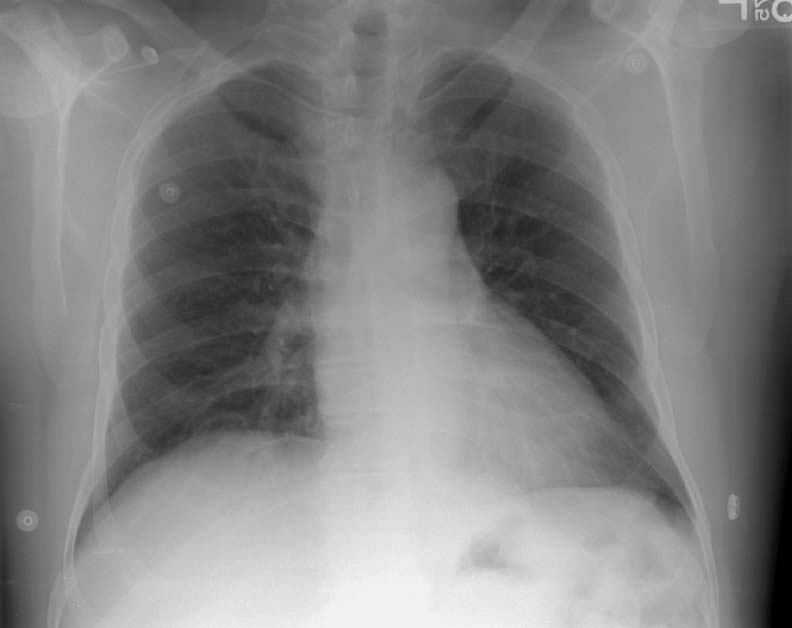

Congenital > Bronchcyst > Images > Cyst1